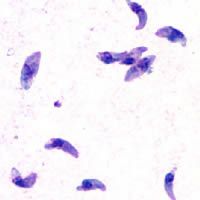

근육포자충과는 톡소포자충아과와 근육포자충아과를 포함하는 콕시듐류의 한 과이다. 근육포자충과는 프렌켈리아속, 근육포자충속, 베스노이티아, 낭포성등포자충, 신장등포자충, 네오스포라, 톡소포자충 등을 포함하며, 이들의 분류 위치에 대한 논의가 있었다. 네오스포라속과 톡소플라스마속은 약 2800만 년 전에 분화된 것으로 추정된다.

성숙한 오오시스트 내부에는 2개의 스포로시스트가 생기고, 그 안에 4개의 스포로조이트가 생기지만, 스티다 소체는 존재하지 않는다. 조직 내에 다양한 크기의 시스트를 생성한다.

시스트 내에 '''브라디조이트'''(완만 증식체, bradyzoite영어)와 '''메트로사이트'''(metrocyte영어)의 두 종류의 세포를 생성한다. 반드시 중간 숙주와 최종 숙주 사이를 왕복하는 생활환을 갖는다. 육포자충속에 100종 이상이 알려져 있으며, 프렌켈리아속이 알려져 있다.[2]

시스트 내에는 1종류의 세포만 포함되어 있다. 톡소플라스마과(Toxoplasmatidae|톡소플라스마티대영어)로 독립적으로 취급하는 경우도 있다. 총 수십 종이 알려져 있다.[2]